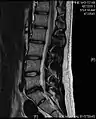

- Magnetic resonance imaging is the gold standard study for confirming a suspected LDH. With a diagnostic accuracy of 97%, it is the most sensitive study to visualize a herniated disc due to its significant ability in soft tissue visualization. MRI also has higher inter-observer reliability than other imaging modalities. It suggests disc herniation when it shows an increased T2-weighted signal at the posterior 10% of the disc. Degenerative disc diseases have shown a correlation with Modic type 1 changes. When evaluating for postoperative lumbar radiculopathies, the recommendation is that the MRI is performed with contrast unless otherwise contraindicated. MRI is more effective than CT in distinguishing inflammatory, malignant, or inflammatory etiologies of LDH. It is indicated relatively early in the course of evaluation (<8 weeks) when the patient presents with relative indications like significant pain, neurological motor deficits, and cauda equina syndrome. Diffusion tensor imaging is a type of MRI sequence used for detecting microstructural changes in the nerve root. It may be beneficial in understanding the changes that occur after herniated lumbar disc compresses a nerve root, and might help in differentiating the patients that need surgical intervention. In patients with a high suspicion of radiculopathy due to lumbar disc herniation, yet the MRI is equivocal or negative, nerve conduction studies are indicated.[44] T2-weighted images allow for clear visualization of protruded disc material in the spinal canal.

MRI scan of large herniation (on the right) of the disc between L4 and L5 vertebrae

A rather severe herniation of the L4–L5 disc

Example of a herniated disc at L5–S1 in the lumbar spine